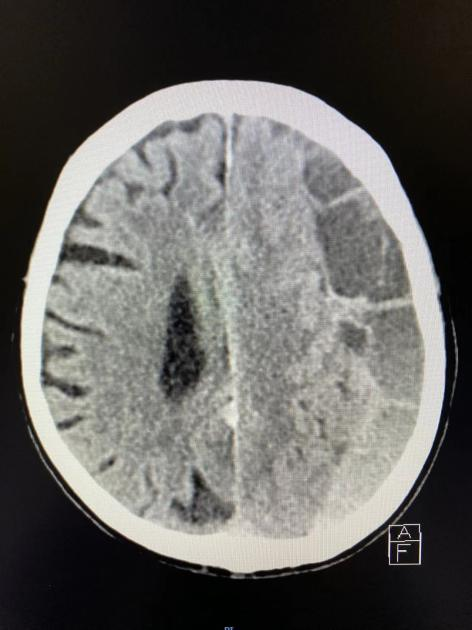

12 月 13 日,他接到刚值完发热门诊夜班的神经外科杨帆医生电话:急诊收治了一位 83 岁高龄的老人,送到医院时人已经意识不清。CT 显示颅内出血量很大,估计在 80-100 毫升。老人核酸检查阳性,同时肺部 CT 显示有斑片状阴影,符合早期新冠肺炎特征。

「比起新冠,先要解决老人颅内出血问题。」常鹏飞表示,老年人大脑萎缩,颅腔比较大,但出血量非常多,最危险的情况下,老人会出现脑疝,威胁生命安全。